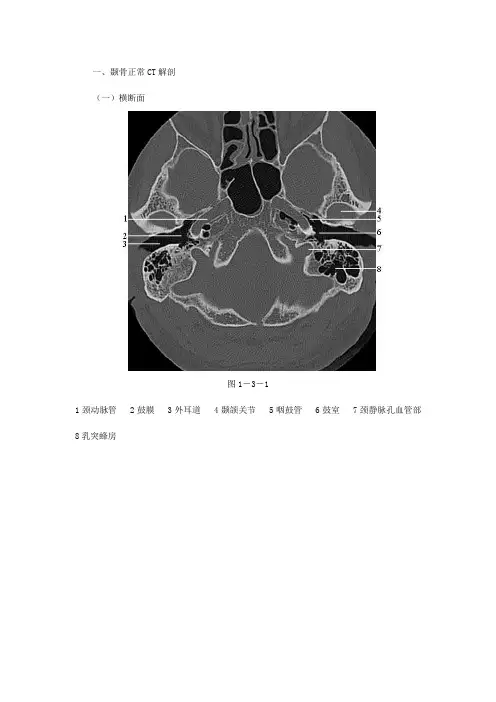

一、颞骨正常CT解剖(一)横断面图1-3-11颈动脉管 2鼓膜 3外耳道 4颞颌关节 5咽鼓管 6鼓室 7颈静脉孔血管部8乳突蜂房图1-3-21耳蜗 2鼓室 3耳蜗水管 4砧骨长脚 5锤骨颈 6外耳道 7蜗窗 8面神经管乳突段9颈静脉窝图1-3-31锤骨颈 2砧镫关节 3面神经管后膝 4鼓室窦 5耳蜗 6匙突 7镫骨 8锥隆起9耳蜗水管图1-3-41内耳道 2耳蜗 3面神经管鼓室段 4前庭窗 5锤骨头 6锤砧关节 7砧骨短脚8前庭 9后半规管图1-3-51面神经管迷路段 2面神经管膝部 3内耳道 4前庭导水管 5前庭 6窦入口7外半规管 8后半规管 9岩鳞隔 10乳突窦1上半规管 2后半规管 3上半规管 4总脚 5弓下管(二)冠状面图1-3-7 1耳蜗 2颈动脉管 3岩枕缝 4鼓室1Prussak间隙 2耳蜗 3颈动脉管 4岩枕缝 5面神经管膝部 6鼓室盾板 7锤骨1耳蜗 2锤骨柄 3鼓膜 4面神经管迷路段 5面神经管鼓室段图1-3-101上半规管 2岩鳞隔 3外半规管 4砧镫关节 5前庭窗 6镰状嵴 7前庭8面神经管鼓室段 9耳蜗1上半规管 2前庭 3外半规管 4蜗窗龛图1-3-121岩乳管 2上半规管 3外半规管 4锥隆起 5颈静脉窝 6总脚 7面神经管第二膝8鼓室窦1枕大孔 2面神经管乳突段 3舌下神经管 4后半规管 5颈静脉结节(三)斜矢状面:图1-3-141前庭水管 2乳突气房 3乙状窦 4内耳道 5颈动脉管 6颈静脉窝图1-3-151上半规管 2后半规管 3前庭水管 4乳突气房 5乙状窦 6总脚 7耳蜗 8镰状嵴9颈动脉管 10单孔 11颈静脉窝1上半规管 2前庭 3外半规管 4后半规管 5前庭上神经管 6面神经管迷路段 7耳蜗图1-3-171上半规管 2外半规管 3面神经管后膝 4面神经管乳突段 5面神经管前膝 6面神经管鼓室段 7鼓室 8茎乳孔图1-3-181砧骨体 2窦入口 3乳突窦 4砧骨短脚 5鼓后棘 6锤砧关节 7锤骨头 8锤骨柄9岩鼓裂10鼓前棘1乳突气房 2外耳道 3颞颌关节。